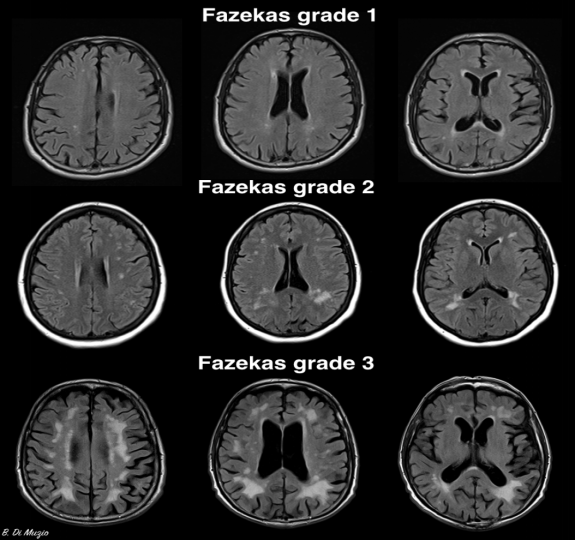

脑白质病变也是分等级的。Fazekas医生在1987年提出了Fazekas视觉评分,是目前公认的、通用的评价脑白质病变严重程度的量表。临床中为了方便,目前常用改良Fazekas法(3级):

Fazekas 1 级:斑点样

Fazekas 2 级:斑块样(斑点部分融合)

Fazekas 3 级:斑片样(病变大片融合)